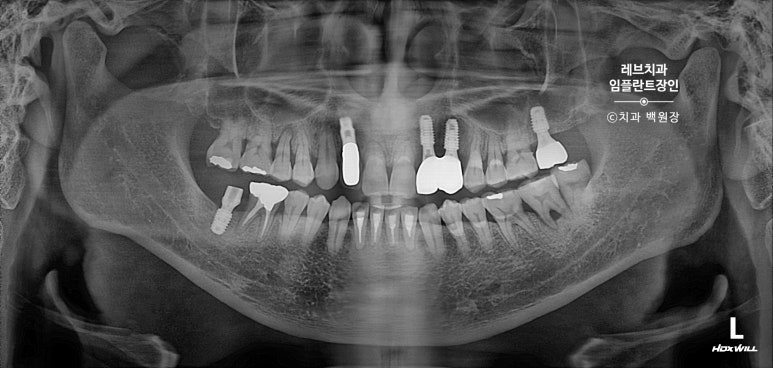

파노라마 엑스레이 사진에서도 알맞게 제작된 임플란트 크라운을 보실 수 있을꺼에요.

깔끔깔끔~~ 임플란트를 심는 것만이 중요한게 아니고, 머리까지 잘 만들어드려야 완성입니다~!

완성 후 촬영한 치과용 방사선 엑스레이 사진에서도, 깔끔하게 완성된 보철물을 보실 수 있을겁니다.